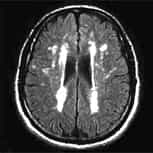

Arnold-Chiari Syndrom Typ I,

idiopathische Skoliose und idiopathische Syringomyelie.